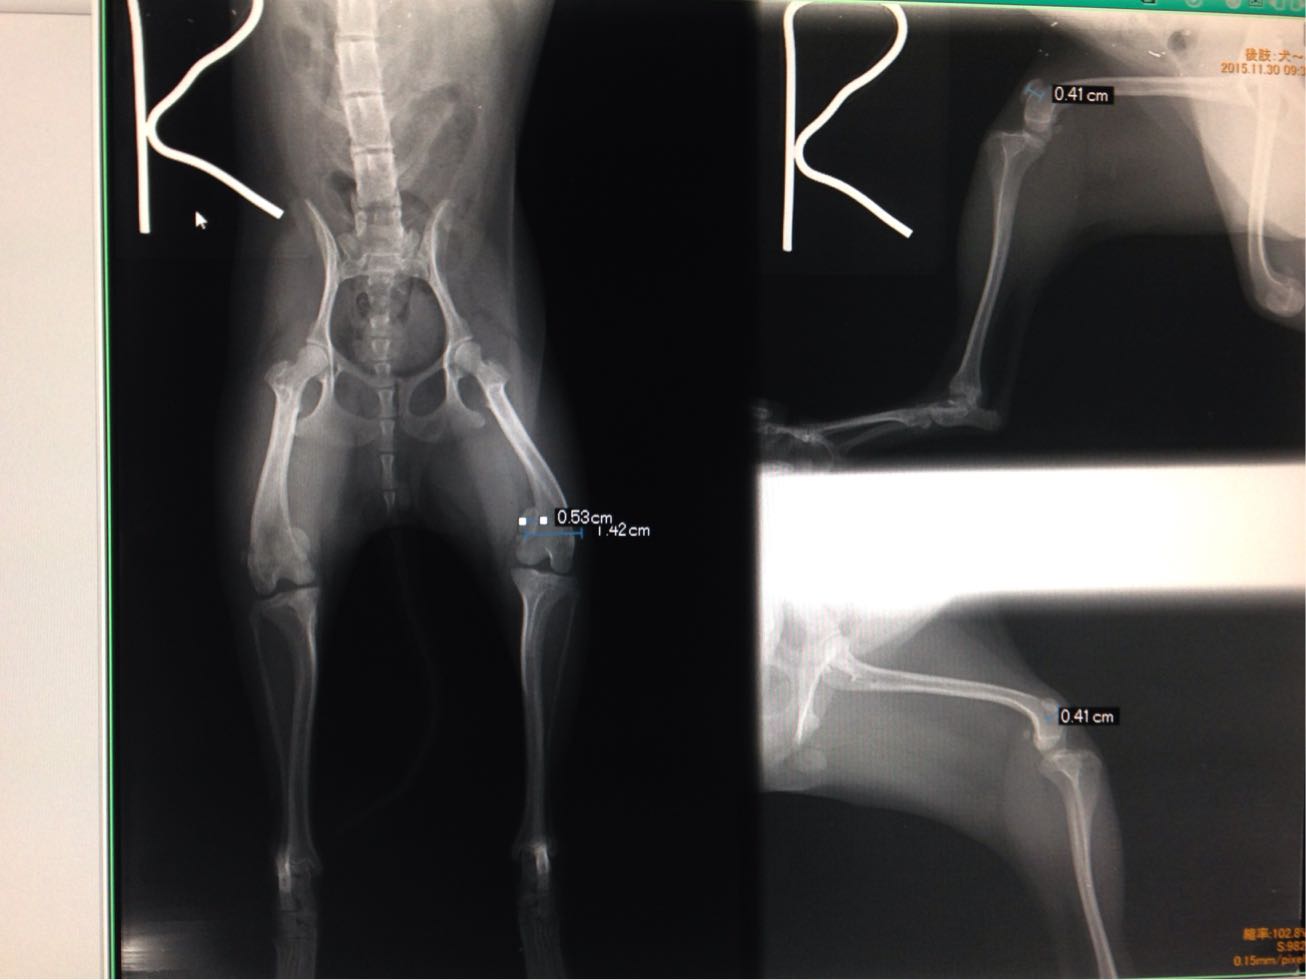

今日はモカちゃんのパテラ手術。

お皿が左右共膝に乗っていません。

問題はモカちゃんの小ささ、体重は1.4キロ膝の骨は14ミリ。

ここに5ミリのお皿を乗せる手術を行うのです、膝下の骨の加工と筋肉のバランス修正も同時に行います。

膝の軟骨をめくり骨を削ります、

軟骨をそこに被せます、

ひざ下の骨を真っ直ぐに修正し、

皿の下にピンを打ち込みズレを防止、

皿が内に落ちるのを防ぐために外側の筋肉を縮めて終了。

そして膝が小さ過ぎお皿はしっかりと溝にはまっていません、

再度の手術が必要かもしれませんね。